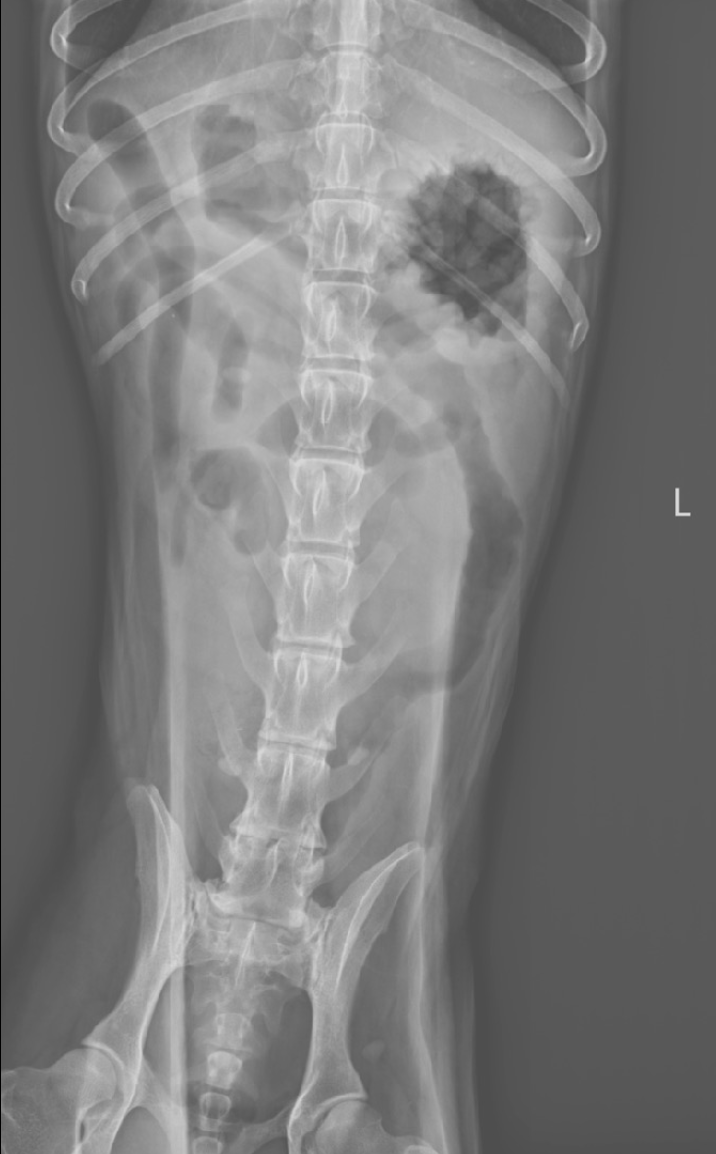

Un Border Collie mâle stérilisé de 9 ans est présenté en consultation pour des vomissements évoluant depuis 48 heures, sans amélioration malgré un traitement symptomatique mis en place initialement (antiémétiques et pansement digestif).

L’animal est abattu et présente une douleur abdominale modérée à la palpation. La température est normale.

Des radiographies abdominales sont réalisées.

L’examen radiographique met en évidence :

• La présence de deux populations d’anses intestinales grêles de diamètres différents :

•  certaines vides

• d’autres dilatées par du gaz et du liquide

Cette distribution est évocatrice d’un iléus mécanique

• Un contenu digestif grêle atypique, visible à droite de la ligne médiane au niveau de L5–L6, caractérisé par un aspect réticulé mêlant gaz et opacité tissulaire

L’aspect est compatible avec la présence d’un corps étranger intraluminal

• Le côlon est modérément dilaté par du gaz

• Une spondylose déformante marquée entre L6 et S1, ainsi qu’entre L6 et L7

Les images sont compatibles avec une obstruction mécanique de l’intestin grêle, très probablement secondaire à la présence d’un corps étranger intraluminal, dont l’aspect est fortement suspect d’un trognon d’épi de maïs.

La spondylose lombo-sacrée observée correspond à une lésion dégénérative chronique incidente, sans lien avec le motif de consultation.

Chez le chien, un rapport entre le diamètre maximal d’une anse grêle dilatée et la hauteur du corps vertébral de L5 supérieur à 1,95 est fortement suggestif d’une obstruction mécanique (80%).